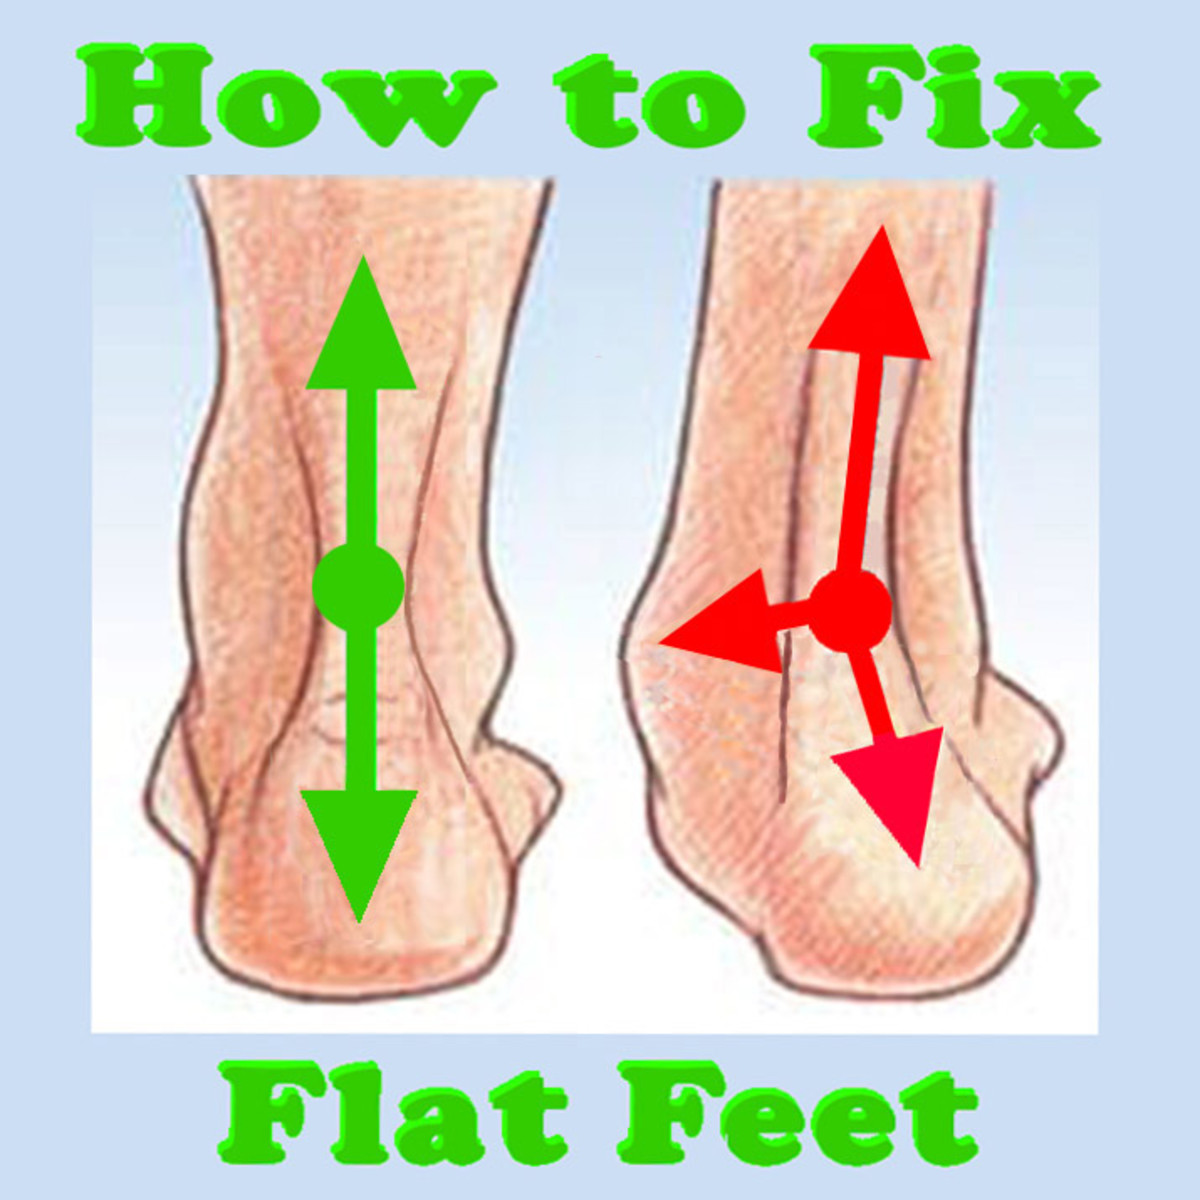

How to fix Flat Feet

How to Fix Flat Feet (With Targeted Exercises) – YouMeMindBody

5 Exercises To Correct Flat Feet

What is and How to Fix Flat Feet